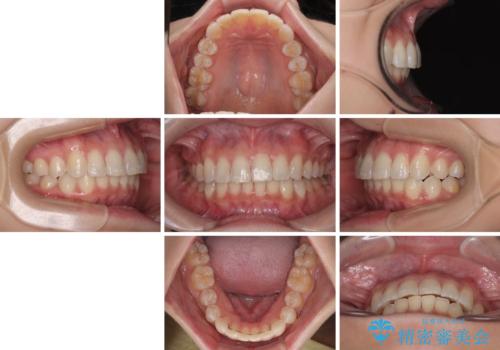

- 上下前歯のデコボコとディープバイトを気にして来院された患者様です。

歯列全体に叢生があり、舌の突出癖が認められたため、突出癖が改善されない場合には口元が突出するリスクが考えられました。

なかなか舌の突出癖が改善できず、上下前歯が非接触となる期間が長く続きました。

アンカースクリューの活用と、舌のトレーニングを何度も指導し、出っ歯になることなく無事に治療を終えることができました。